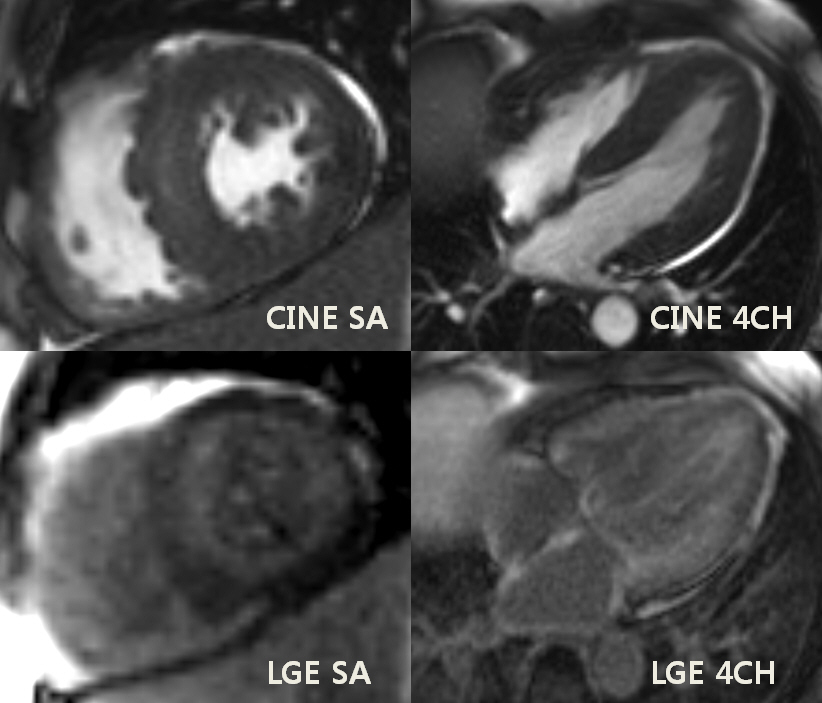

F/53Y, C.C: ECG abnormality at routine check, Q wave at inferior lead, Lower normal LV systolic function (EF 50%)

Jin Young Yoo, Seoul National University Bundang Hospital

HIT : 14528